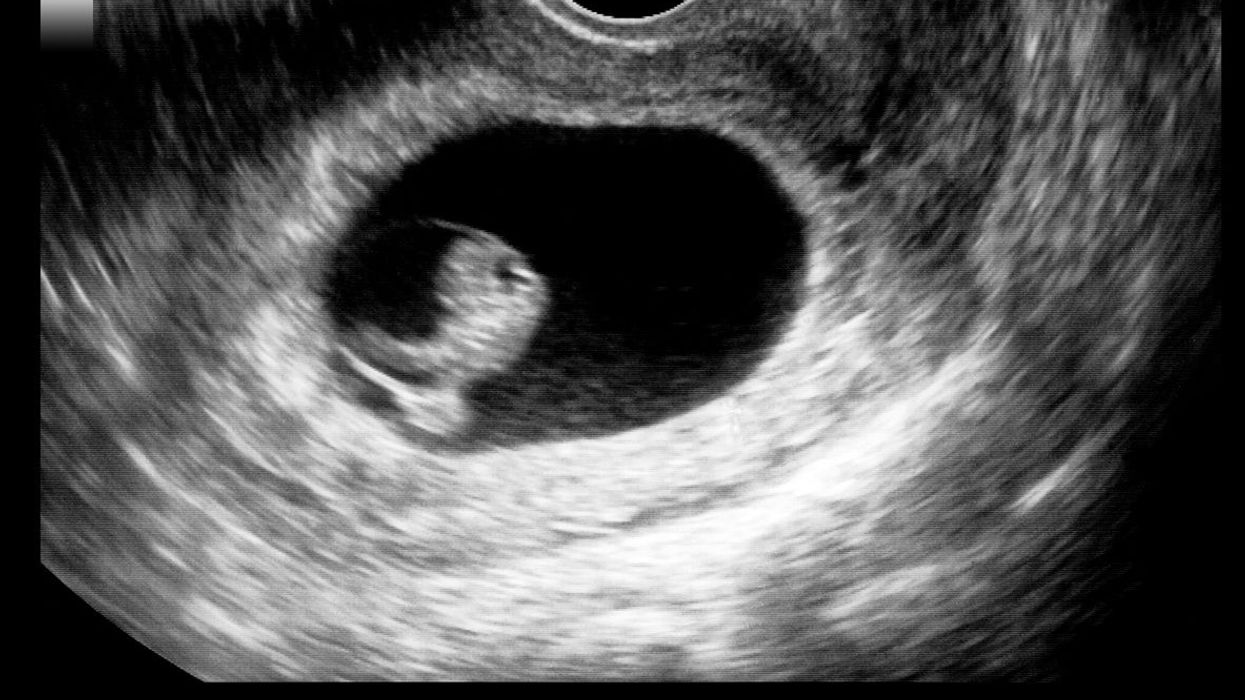

The embryo model, derived from pluripotent stem cells capable of differentiating into various cell types, exhibits a well-organised three-dimensional structure that closely resembles key developmental processes during the initial stages of human embryonic development, according to a study conducted at Cambridge University in the UK.

By allowing experimental modeling of embryonic development during the second week of pregnancy, these innovative models have the capacity to enhance our understanding of the origins of organs and specialised cells, including sperm and eggs.

The second week of pregnancy in humans is when the embryo implants into the uterus. However, this is also the time when many pregnancies are lost.

The new models derived from human stem cells do not have a brain or beating heart, but they include cells that would typically go on to form the embryo, placenta and yolk sac, and develop to form the precursors of germ cells, that will form sperm and eggs.

Many pregnancies fail at the point when these three types of cells orchestrate implantation into the uterus and begin to send mechanical and chemical signals to each other, which tell the embryo how to develop properly.